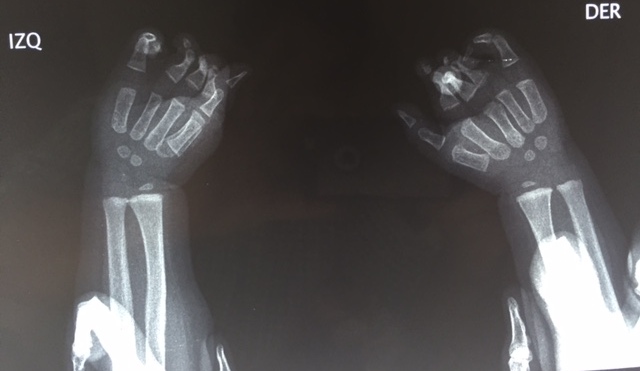

This first photo is Jas Merlyn’s hand her first screening. She has bilateral multi-digit syndactyly by congenital constriction band syndrome. She was too young for surgery on her first screening visit.